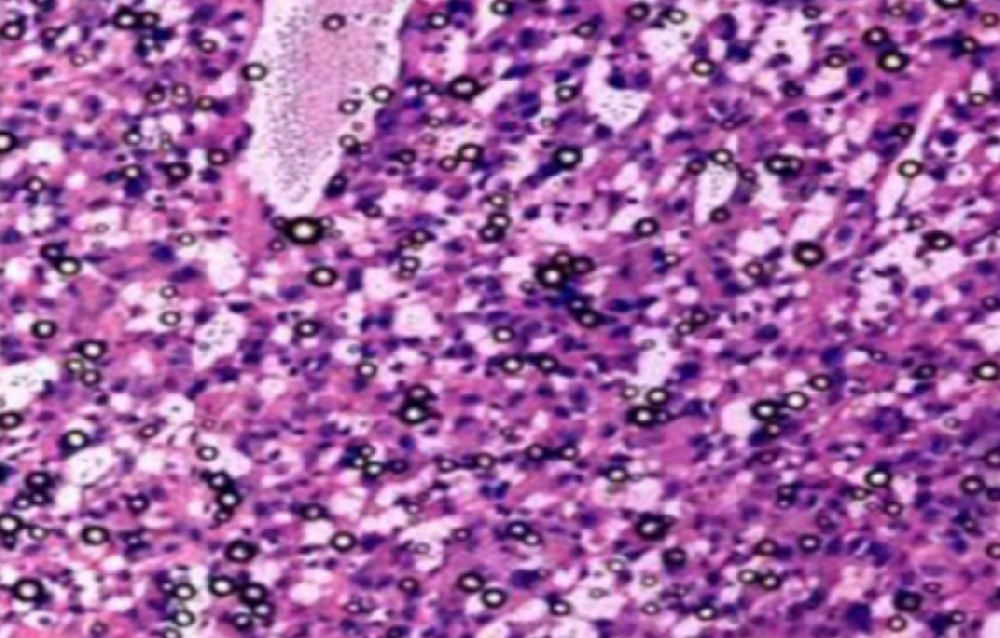

HE染色,全称苏木精-伊红染色法(Hematoxylin and Eosin staining),是最常见的组织切片染色技术之一,用于在显微镜下观察和分析组织或细胞的结构和形态。

虽然HE染色是最常见且最基础的染色技术之一,😭但在实验过程中,很容易出现各种情况导致染色切片质量参差不齐。所以,小编根据以往实验经验,给大家整理归纳出了15个HE染色中的常见问题,还包含问题原因分析以及解决方法哦~

形成原因:切片经梯度乙醇处理后没有完全脱水,导致二甲苯透明、中性树胶封固后残留大量水分。 解决方法:首先移去盖玻片,用二甲苯溶解封固剂如中性树胶,再将切片置入无水乙醇内,待切片重新脱水完全后,用二甲苯透明处理,中性树胶封固。要注意所有用于脱水和透明的液体,在使用一定时间后,应及时更换。 二、细胞核呈红、棕色 形成原因:苏木精染色液过度氧化,切片在苏木精染液染色后返蓝不足。 解决方法:每次染色之前检查苏木精染色液的染色能力,发现苏木精染色液氧化过度应及时更换。此外,切片经苏木精染色后,要给切片以足够的蓝化时间,蓝化过程可用流水、温水、弱碱性溶液(如稀氨水或0.2%碳酸氢钠)等处理。 三、切片在脱蜡后出现大片白色斑点 形成原因:由于烤(烘)片温度太低,切片上的组织蜡膜在脱蜡前没有充分烤(烘)融化。或是因为切片在二甲苯液中停留时间不足,或二甲苯使用过久,造成的脱蜡不彻底。 解决方法:若是由于切片烤(烘)温度低所致,可以先用二甲苯去除切片上的封固胶,然后重新用二甲苯脱去切片上的石蜡,再进行后续染色。若是由于切片在脱蜡的二甲苯中停留时间不足或脱蜡二甲苯使用过久浓度不足所致,则需将切片退回到二甲苯中,停留较长时间,或更换二甲苯液体重新脱蜡,再入乙醇重新脱二甲苯,入0.5%盐酸水溶液褪色后,重新HE染色。 四、细胞核苍白暗淡,即苏木精染色太淡 形成原因:切片在苏木精染色液停留时间太短;苏木精染色液过度氧化,失去染色能力,不能再继续使用;分化步骤处理时间过长;固定不及时。此外值得注意的是,若骨组织细胞核暗淡,大多是脱钙过度造成的。 解决方法:切片重新染色。如果组织在酸性固定液(如Zenker、Bouin)或非中性缓冲甲醛液固定时间过长,细胞核染色能力将减弱,需增加其在苏木精染色液的时间,或用一些方法增加组织的嗜碱性,以改善细胞核的着色。例如,上述组织玻片可以使用Weigert铁苏木精染色液。如果组织是用Zenker液固定的,可将切片脱蜡后放在5%碳酸氢钠溶液3~4h,流水冲洗5min后染色。如果组织是用Bouin液固定的,可将切片脱蜡后放在5%碳酸锂1h,流水冲洗10min后染色。 五、细胞核过染,苏木精染液占据了细胞质 形成原因:玻片在苏木精染色液停留时间过长,或是切片太厚、分化步骤时间太短。 解决方法:如果不是因为切片太厚(用显微镜仔细上下微调,只有一二层细胞核层次),就需将切片进行脱色、漂白、重新染色,适当调整染色和分化时间。但如果确定是由于切片太厚导致的细胞核过染,则需要重新切片。 六、伊红着色淡 形成原因:可能是伊红染液pH值大于5,也可能是蓝化液残留过多,切片太薄,或是切片经伊红染色后在乙醇脱水时间过长。 解决方法:检查伊红染液pH值,必要的话,用乙酸将其调节在4.6~5.0之间,从而使伊红染色色彩艳丽。此外,确保每次蓝化步骤完成后,使用的弱碱性溶液被充分洗去,玻片上没有残留的弱碱性溶液。最后,检查切片的厚度,且脱水时不要让切片在低浓度乙醇中停留时间过长,因为含水多的低浓度乙醇会将切片伊红的颜色分化掉。 七、细胞质过染、分色不足 形成原因:伊红染色液浓度太高,特别是存在焰红燃料、四溴四氯荧光素钠。切片在伊红染色时间过长,或是切片在伊红染色后经乙醇脱水步骤时时间太短,而使乙醇分化伊红的作用不能产生,都能够使细胞质过染。 解决方法:适当稀释伊红染色液,减少伊红染色时间,或使切片在乙醇脱水等步骤时,停留时间相对均匀。同样,也要检查切片的厚度是否合适。 八、切片中出现蓝黑色沉淀物 形成原因:苏木精染色液中的金属膜黏附在玻片上。 解决方法:染色前仔细过滤苏木精染色液,建议使用半氧化苏木精染色液,如Gill苏木精染色液,可以避免过多的金属膜产生。 九、光镜下切片某些区域难以聚焦 形成原因:盖玻片上可能有封固切片的封固剂。 解决方法:移去盖玻片,重新用干净的盖玻片封片。检查切片封片方法,是人工手工封法,还是机器自动封法,如有问题及时调整。 十、封固剂从盖玻片与载玻片之间的缝隙回缩 形成原因:盖玻片弯曲或不平整,或是封固剂含二甲苯过多,稀释过度。 解决方法:移去盖玻片,重新找一张盖玻片,用干净的封固剂封片。如用手工封片法,保证在封固结束时,封固剂容器盖子为紧闭状态。且尽量使用小的容器盛装封固剂,一旦封固剂太黏稠,就可以选择废弃。 十一、细胞核呈灰蓝状态 形成原因:可能由于组织处理温度过高、过热,在液体石蜡中停留的时间过长。或是固定时间太短后,直接在高浓度的乙醇中进行了脱水处理。 解决方法:理论上来说,仅在组织浸蜡步骤才进行加热,组织不能在热蜡液中停留太久。如果由于某些原因不能进行下一步包埋处理,可将组织连同塑料包埋盒一并放置在室温空气中,冷却凝固,以备包埋。待需要包埋时再重新加温直至石蜡融化即可。组织在处理前必须确保固定良好,脱水最好能从低浓度的乙醇开始。 十二、类色素的点状结晶和黑色光滑细胞核 形成原因:这种裸核改变是因为切片封片前放置在空气中的时间太长,以至于二甲苯挥发,切片干燥。 解决方法:移去组织切片上的盖玻片和封固剂,重新处理。将切片水洗数分钟,然后重新脱水、透明、封固。封片过程中要保持组织切片的轻度湿润,尽量不要让其干燥。 十三、染色过淡或过浓 解决方法:如果染色过淡,可以增加染色剂的浓度、延长染色时间或更换新鲜的染色剂;如果染色过浓,则应减少染色剂的浓度或缩短染色时间。 十四、切片出现叠加褶皱 形成原因:新购买的玻片洁净度不够、用镊子撑开切片时操作不够熟练未能平整伸展,或玻片表面有油脂,切片粘贴不牢。另外,烤片时间不足、烤片温度过低或切片过厚造成切片脱落,都会造成重叠或有皱褶的情况。 解决方法:新购买的玻片最好能用硫酸清洁液浸泡一晚,然后流水冲洗干净。在适宜的温度下烤片时间宁长勿短,保证有充足的烤片时间和温度。另外,切片刀要锋利,才能切出厚薄适宜的切片,保证切片不会因为过厚而脱落。 十五、组织残缺不全或有刮划痕迹 形成原因:组织残缺不全是由于切片时修整蜡块时深度不够、组织没有全部暴露于切面。切片的刮划痕迹是由于切片刀的刀锋有缺口、包埋的组织有异物,或是钙化组织、骨组织及包埋石蜡有沙粒造成的。 解决方法:修整蜡块时保证组织块全部暴露于切面,切片时保证切片刀的锋利没刀口。同时在组织取材时去除手术异物和钙化组织。最后,骨组织要完全脱钙,这样可以保证切片的完整和平整美观。 *注:由于实验中导致结果出现误差的原因多种多样,以上内容仅供参考,具体根据实际情况进行判断。